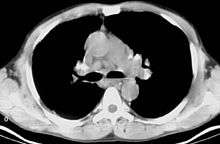

CT scan of the chest showing bilateral lymphadenopathy in the mediastinum due to sarcoidosis.